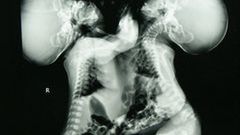

Po przyjściu na świat bliźniąt okazało się, że dzielą ze sobą 30 procent płatu czołowego mózgu i wiele ważnych naczyń krwionośnych. Wykluczało to ich rozdzielenie.

Bliźniąt nie można rozdzielić, ponieważ są zrośnięte płatami czołowymi mózgu, dzielą też wiele ważnych arterii. Lori i George nauczyli się jednak żyć ze swoją przypadłością. Twierdzą, że prowadzą dwa zupełnie oddzielne życia. Lori była w kilku związkach, a George zdecydował się na zmianę płci.